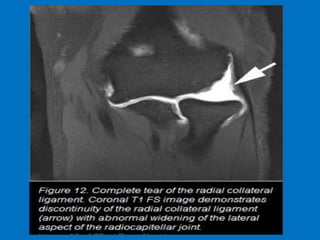

Complete tear of the LUCL.